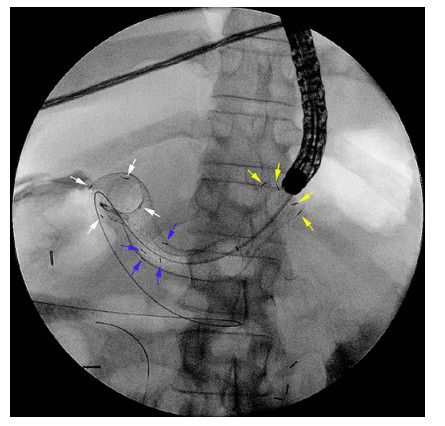

Abstract: Self-expandable metal stents (SEMSs) are frequently utilized for palliation of malignant gastric and/or duodenal outlet obstruction (GDOO). Re-establishing luminal patency with accurate SEMS positioning while limiting migration and adjacent tissue injury is an important technical consideration and aim. The duodenal HANAROSTENT® was introduced in the USA in 2019 and developed with these challenges in mind. As the first center in the USA to deploy the duodenal HANAROSTENT® in clinical practice, we herein examine our early experience with its use. Specifically, we describe 7 consecutive cases of malignant GDOO in which a duodenal HANAROSTENT® was placed for on-label use, defined as palliative treatment of malignant gastric and/or duodenal obstruction. All stents were 22 mm in diameter, with 5 being 90 mm and 2 being 120 mm in length. Technical and clinical success with duodenal HANAROSTENT® placement were achieved in all 7 cases (100%). In no case was stent adjustment required post-deployment. There were no stent-related adverse events, and no subsequent endoscopic procedures were necessary in any of the patients during a mean follow-up of 5 months (range 1–12 months). In summary, the duodenal HANAROSTENT® appears to perform well and be a promising alternative to other available duodenal SEMSs. As experience in the USA with this newly introduced duodenal SEMS grows, multicenter prospective data should be collected to better establish its relative safety and efficacy.